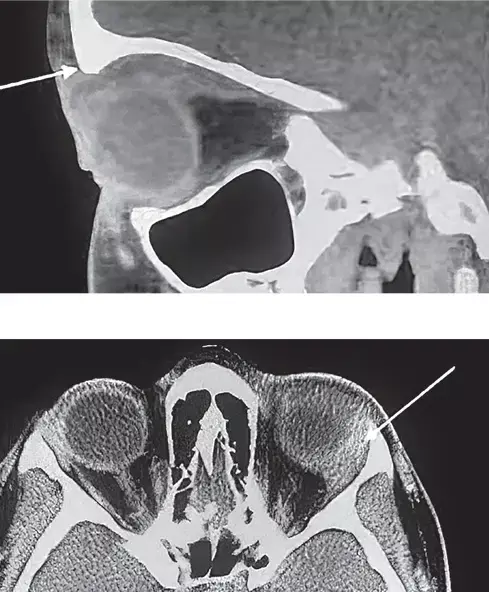

Рисунок 13. КТ орбит и головного мозга.— Жалобы у девочки возникли резко за 4 дня до госпитализации. Офтальмологом по месту жительства направлена к нам с диагнозом «глаукома», хотя признаков глаукомы нет, — отметила врач. — На УЗИ мы видим кистозное образование за глазным яблоком без признаков кровотока. Вены слева расширены, несколько извиты. В остальном глазное дно без каких-либо изменений. На КТ определяется картина неоднородного жидкостного образования левой глазницы 2,2×1,7×2,6 см (см. рис. 13). Глазное яблоко смещено вниз и кпереди и не накапливает контраст. Складывается впечатление о наличии горизонтального уровня разделения сред со смещением более плотного компонента вниз.

По заключению КТ глазницы с внутривенным болюсным контрастированием в верхне-медиальном отделе правой орбиты определяется объемное образование 2,8×1,9×1,1 см с четкими и ровными контурами, жидкостной плотностью до 15 HU, не накапливает контрастный препарат.

На МРТ видно, что новообразование состоит из двух частей, одна из которых кистовидная, а другая гипоэхогенна по отношению к мозговой ткани. Образование вызывает компрессию мышц глаза, смещает зрительный нерв.